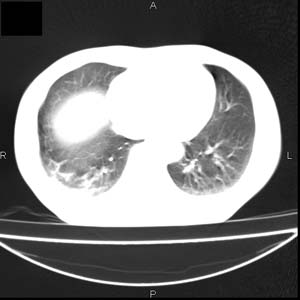

患者男,50岁,在高速公路上发生车祸来查头颅及胸部。查体双下肢感觉障碍。我看着好象气管有异物且有一个胸椎有骨折,但椎周软组织不对劲,请大家看看。

上传骨窗及肺窗 不然不好定骨折,双侧胸腔少量积血。

结合病史考虑胸椎挫伤及椎旁血肿,右下肺挫伤.建议mri.

双侧胸腔少量积血,t4-5椎旁软组织肿胀。

结合病史考虑胸椎挫伤及椎旁血肿,右下肺挫伤.建议mri

结合病史考虑胸椎挫伤及椎旁血肿。随访复查吧,有的病人会发生迟发性椎体压缩骨折。